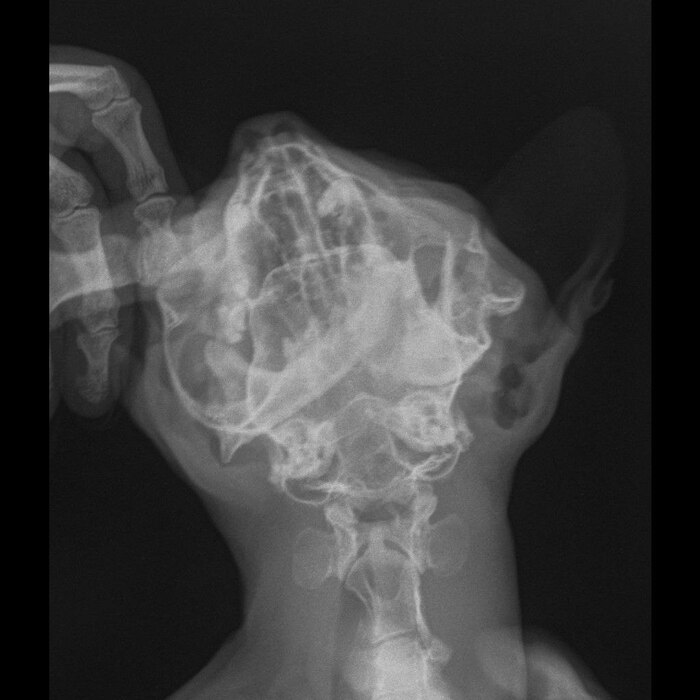

Здравствуйте. Читающие пост ветеринарные врачи, разбирающиеся в снимках рентген, помогите информационно, высказав свое компетентное мнение в комментарии. На снимке кот. Челюсть вывернута 22 июня 2025 года. Варианты исправления и кто мог бы это сделать. Варианты с учетом всех возможных последствий.

Информация собирается по всем источникам для принятия решения о дальнейших действиях.